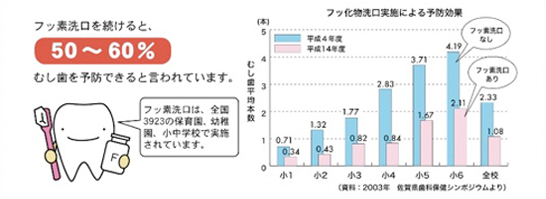

フッ化物洗口Fluorine

ブクブクうがいがむし歯を予防

フッ化物洗口をおすすめします!

フッ化物洗口の効果は?

ご家庭でフッ化物洗口をしましょう

- フッ化物洗口は一日一回、寝る前の歯みがき後に行うのが効果的です。

- 4歳以上のすべての方(ぶくぶくうがいが出来る方)がご利用できます。